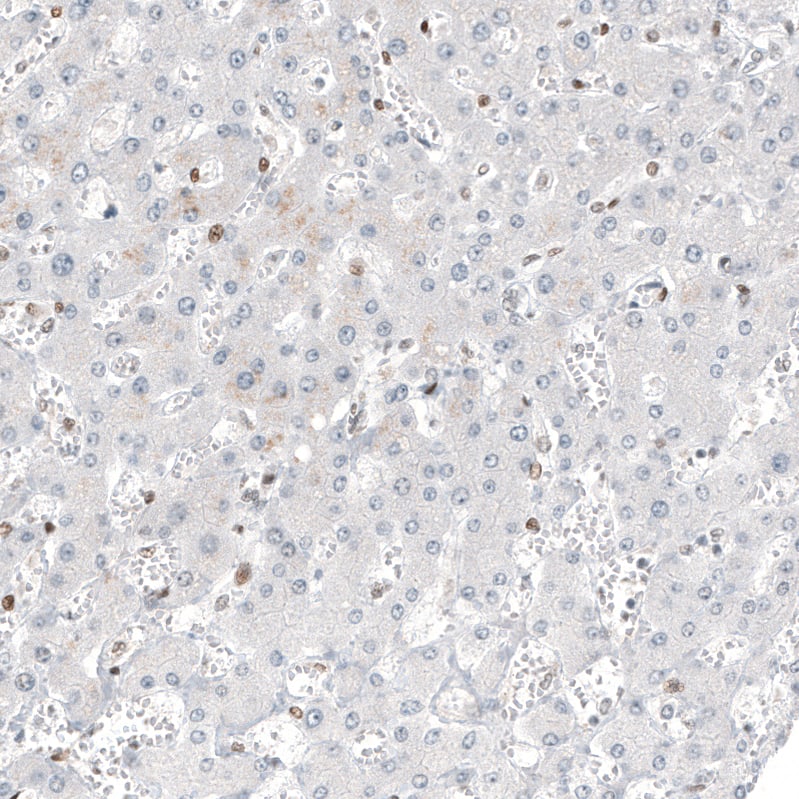

Staining of human liver shows no positivity in hepatocytes as expected.